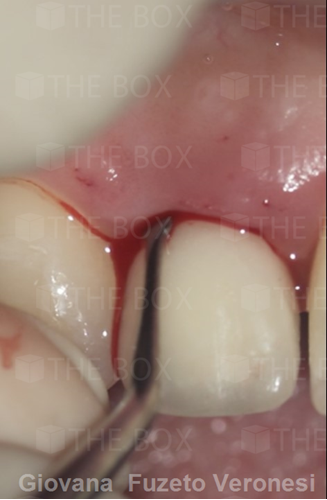

Infra bony defect one wall defect follow up 18 months show regeneration of buccal bone and interdental defect utilizing allograft bone substitute